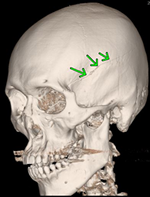

左側頭部を強打した脳挫傷の事例

CTの3D画像では骨折線が確認できます。CT画像では矢印のところに異常があります。

自転車に乗っていたところ、軽自動車と出合い頭で衝突した被害者のものです。左側頭部を骨折し、その衝撃により、打撲部位の直下の脳組織が挫滅となりました。これも、局在性の脳挫傷です。